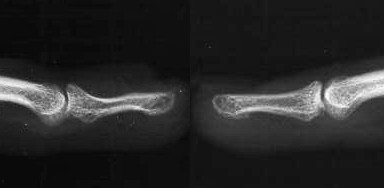

Plain films confirmed a concave contour deformity of the dorsal aspect of the distal phalanx, shown here compared to the opposite, normal finger film: